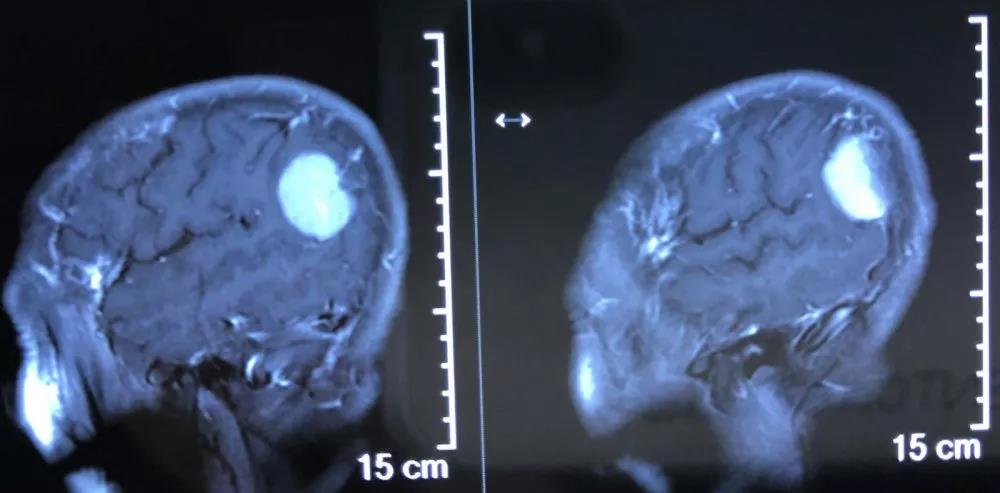

患者女,74岁,头痛、头晕20年,加重4天,于2020年1月14日入院。

1.右顶叶脑膜瘤;2.脑缺血灶;3.慢性萎缩性胃炎。

入院后给予Ⅰ级护理,消肿止痛等对症治疗,行术前准备,择期手术治疗。患者于1月23日在全身麻醉下行右顶枕部开颅脑膜瘤切除术,肿瘤大小约3×2×2.5cm。患者术后恢复良好,无任何神经功能障碍,复查颅脑MRI增强扫描提示肿瘤全切。